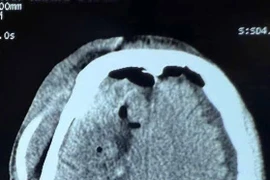

Từ các kết quả chẩn đoán hình ảnh cho thấy anh đối diện với những biến chứng do khối u tái phát thần tốc. Một khối u nguyên bào mạch máu (Hemangioblastoma) khổng lồ, dạng hiếm đã chiếm gần trọn vùng tiểu não bên trái.

Kết quả chụp CT-Scanner của bệnh nhân được chụp tại Bệnh viện Đa khoa Quốc tế Minh Anh - Ảnh BVCC